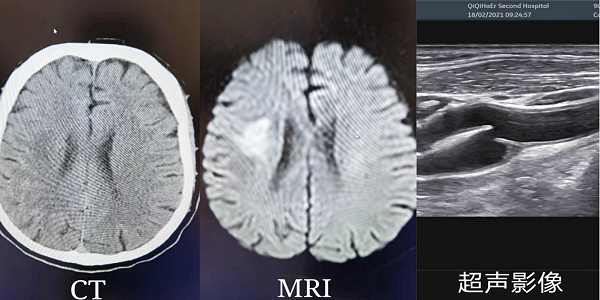

近日,介入科成功为一位右侧“颈动脉蹼伴重度狭窄”罕见病患者完成颈动脉支架置入术。62岁的李先生,因“反复言语不清”来我院神经内科三病区就诊。经影像CT、MRI、电生理头颈血管筛查及CTA提示:右侧半卵圆中心急性脑梗死、右侧颈内动脉起始部颈动脉蹼形成、颈动脉重度狭窄。随后,神经内科三病区立即与介入科展开会诊,讨论结果为患者是由于右侧颈动脉蹼伴重度狭窄,血液在病变处产生涡流,易形成赘生物,由于血流动力学原因,将栓子冲击到颅内,产生脑梗死。如果不及时进行介入治疗,病人会反复发生脑梗死,可能导致半身不遂或危及生命。

影像检查提示右侧颈内动脉起始部颈动脉蹼形成